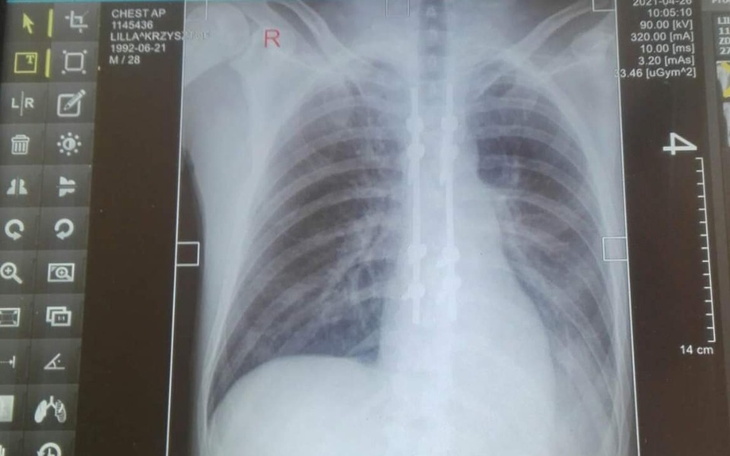

Brat jest po bardzo poważnej operacji na kręgosłup po upadku z dachu podczas pracy brat już do końca życia nie będzie chodzić potszebe są też leki ponieważ pod czas upadku doznał wiele uszkodzeń wielo narzędziowe ma orzeczenie o niepełnosprawność ale każdy wie ile się dostaje za takie pieniądze nie starczają dla osób po wypadkach każda pomoc będzie wdzięczna